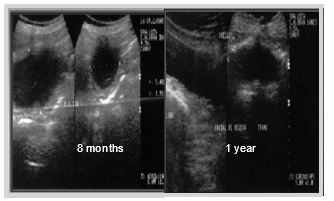

Evolution: The patient's progress occurs without significant clinical signs, except for mild hematuria. Symptomatic and ultrasonographic follow-up at 4, 6 months, and 1 year shows no recurrences (Figures 24) (Figure 25).

Figure 24 Ultrasonographic follow-up at 4 months post-cryosurgery.

Figure 25 Ultrasonographic follow-up at 6 and 12 months post-cryosurgery.